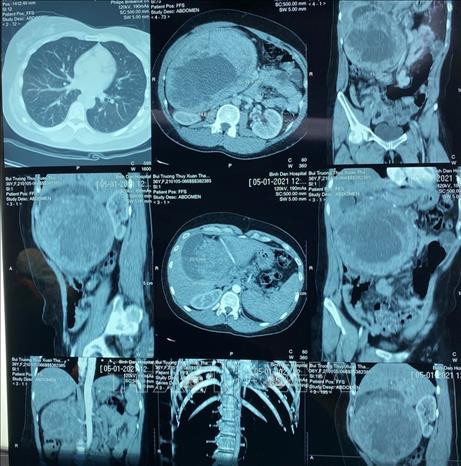

À l'hôpital Cho Rây, après des examens poussés, les médecins ont diagnostiqué une grosse tumeur dans le pancréas de cette patiente.

Le 11 janvier, après les examens adéquats, les médecins ont réalisé une intervention chirurgicale pour enlever la tumeur de cette patiente. "Lors de l'ouverture de l'abdomen de la malade, nous avons constaté que la tumeur avait rempli presque tout l'abdomen droit. Cette tumeur montrait des signes de nécrose à partir du centre, de compression de la veine porte et des veines hépatiques. Nous avons dû élargir l’incision chirurgicale", a déclaré le Dr Doàn Tiên My.

Après 10 heures de chirurgie, les médecins ont enlevé la totalité de la tumeur de 20 cm de diamètre et de 2,2 kg. Il s'agit de la plus grande tumeur du pancréas enregistrée au Vietnam et même dans le monde entier !